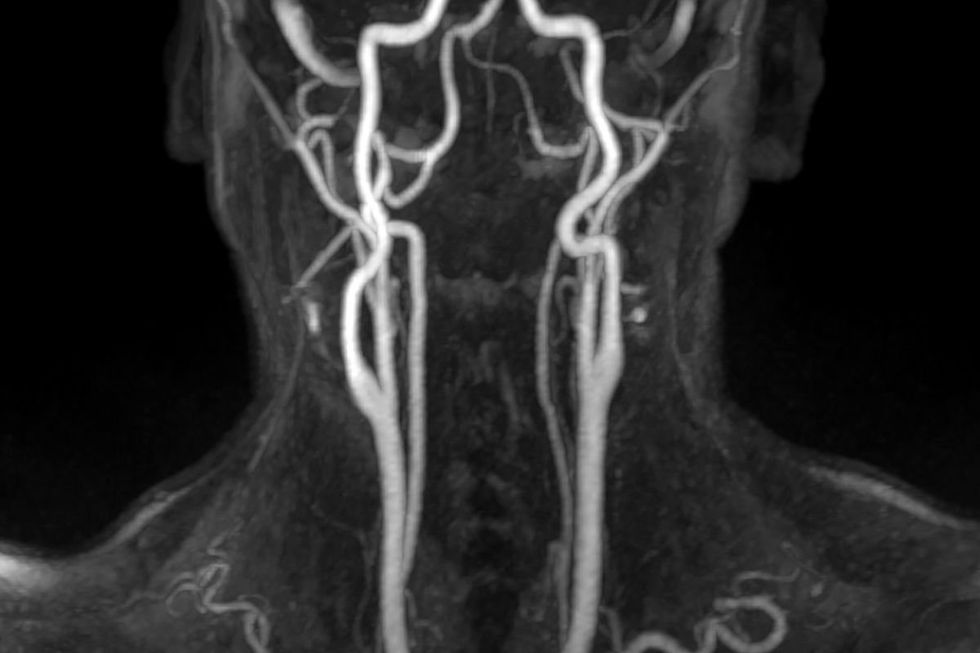

A straightforward neck scan could help identify men who face a higher chance of heart attacks and strokes, according to new research from University College London.

The study suggests that GPs might want to offer these ultrasound scans to patients aged over 60 to assess their carotid arteries - the major blood vessels running up both sides of your neck, which could provide vital clues about heart health.

The scan works by measuring how much the carotid arteries stretch with each heartbeat. When these vessels lose their flexibility, they can't expand properly to accommodate blood flow, which pushes up blood pressure and forces the heart to work harder.